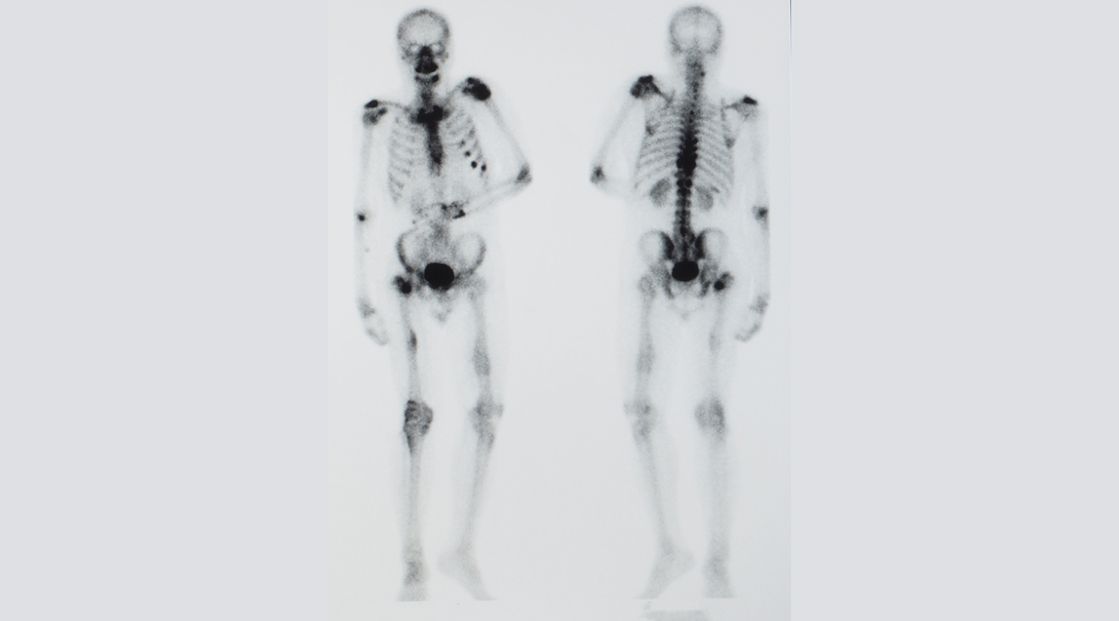

NUT carcinoma (NC) is a rare and highly aggressive tumor that occurs mainly in adolescents and young adults and is defined by the presence of a singular somatic rearrangement in the NUTM1 gene.

To date, standard treatment approaches such as chemotherapy, radiotherapy, and surgery have been successful only in very rare, early-diagnosed cases with highly localized tumors. Targeted approaches, including epigenetic modulators such as so-called BET (iBET) and HDAC inhibitors (HDACi) have failed to improve this disastrous situation. Patients usually die within a few months.

Oncolytic viruses (OV) represent a novel approach that has not yet been tested for the treatment of NC. When using the virotherapeutic agent T-VEC (which has only been approved for melanoma as IMLYGIC®), NC cell lines were found to be highly susceptible and could be killed with great efficiency in the course of virotherapeutic treatment. In the treatment of a very first adult NC patient at UKT, T-VEC was not only very well tolerated, but also replicated at very high rates in the patient's NC tumor cells, leading to profound oncolysis. Treatment of additional NC patients at the UKT (one adult aged 23 years; one child aged 10 years (in collaboration with PD Dr. Ines Brecht from the University Children's Hospital Tübingen) also demonstrated both the safety and efficacy of T-VEC.

On this basis, we are currently initiating the world's first phase I study to investigate additive T-VEC immunoVirotherapy of NUT carcinomas as part of multimodal therapeutic regimens. To further enhance the antitumor immune response, the immune checkpoint inhibitor pembrolizumab will be added to each application of T-VEC (as has already been done in all three UKT NC patients).